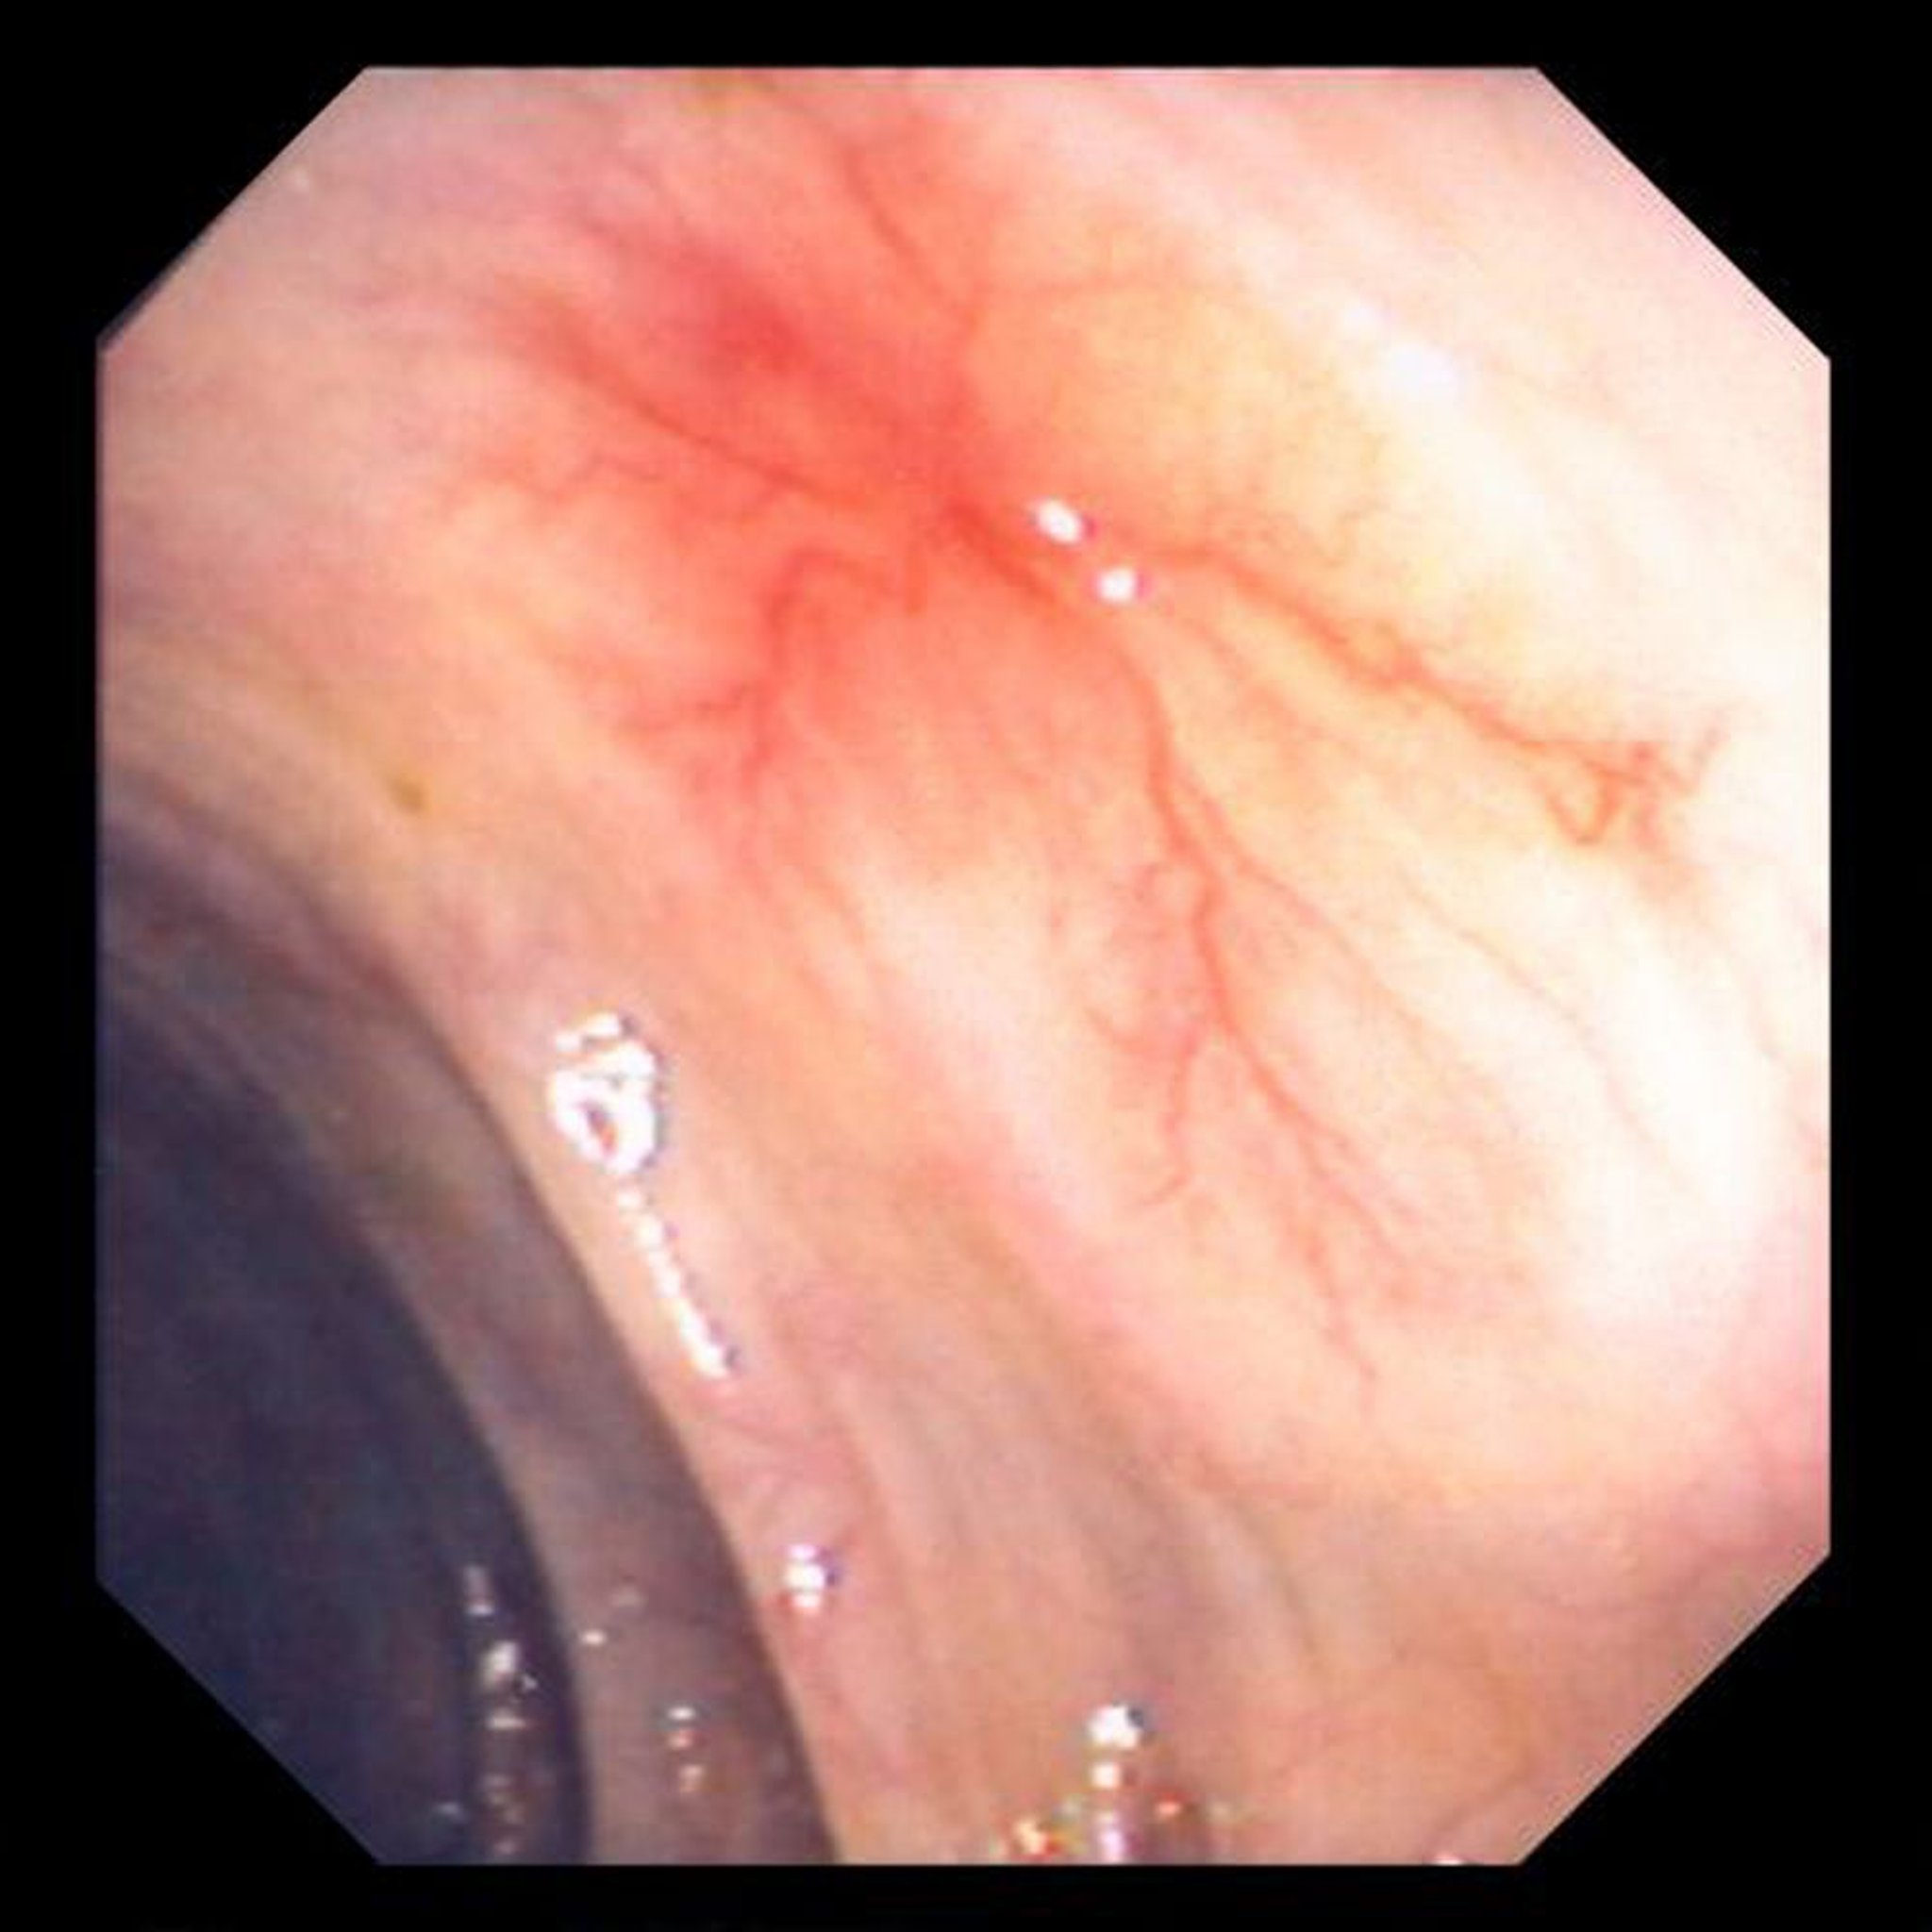

Questa foto mostra ectasia vascolare della parete dell'intestino.

Image provided by David M. Martin, MD.